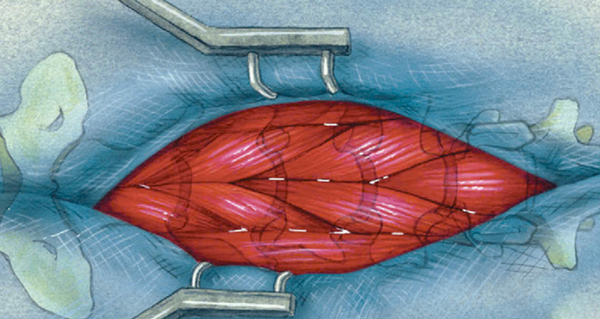

Sau khi xác định chính xác vị trí đốt sống cổ C3 và C4, tiến hành tách cơ dài cổ, từ đó bộc lộ rõ đĩa đệm C3 – C4, tạo điều kiện cho các bước phẫu thuật tiếp theo.

Hình trên minh họa quá trình phẫu thuật cắt bỏ đĩa đệm từ đường bụng. Khi sử dụng khoan tốc độ cao, cần mài nhiều hơn theo hướng phía trước của cột sống cổ, vì hướng nhô lên của đĩa đệm là từ phía sau bụng ra phía sau. Điều này giúp tiếp cận vùng tổn thương một cách chính xác, giảm nguy cơ tổn thương các cấu trúc quan trọng xung quanh.

Lưu ý khi sử dụng khoan tốc độ cao trong phẫu thuật cắt bỏ đĩa đệm cổ:

- Chiều rộng mài mòn không nên vượt quá một nửa chiều rộng của thân đốt sống. Nếu vượt quá, sự ổn định của cột sống sẽ bị suy giảm, làm tăng nguy cơ biến dạng hoặc mất vững.

- Tôi đặc biệt ưa chuộng máy khoan tốc độ cao Bailu, vì nó không chỉ quay nhanh, ổn định, an toàn, mà còn có chức năng dừng khẩn cấp—một yếu tố cực kỳ quan trọng trong phẫu thuật.

- Khi khoan ở tốc độ cao, chắc chắn sẽ có một số mô mềm bị cuốn vào. Nếu không có chức năng dừng khẩn cấp, có thể kéo theo cả mạch máu, dây thần kinh, gây tổn thương nghiêm trọng, thậm chí đứt hoàn toàn. Những sai sót như vậy có thể dẫn đến thảm họa trong phẫu thuật.